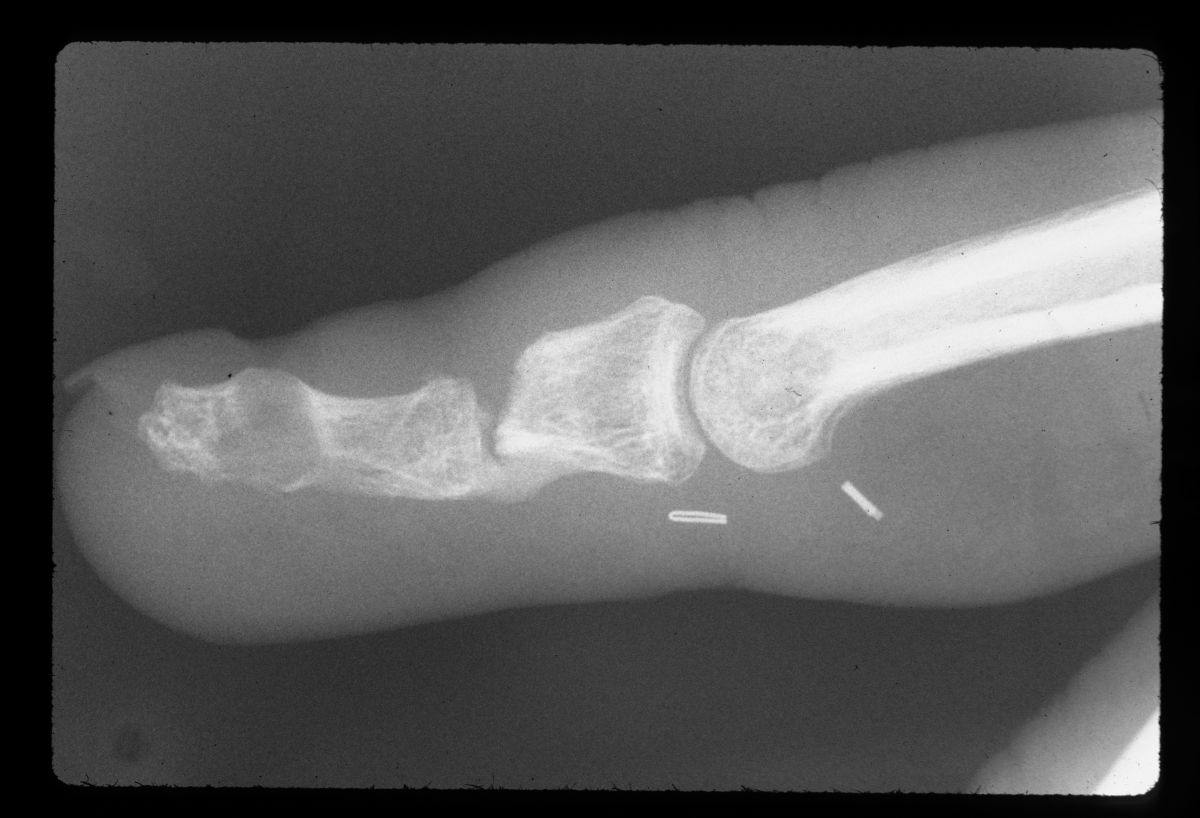

| Late films show only palmar cortical bridging and a lucency in the distal phalanx which was visible in the original films, consistent with an epidermal inclusion cyst. The patient admitted to many open and crushing fingertip injuries over the years in his line of work. |